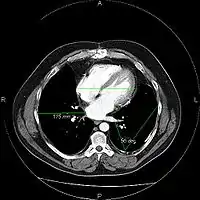

The same image following contrast adjustment, sharpening and measurement tags added by the system